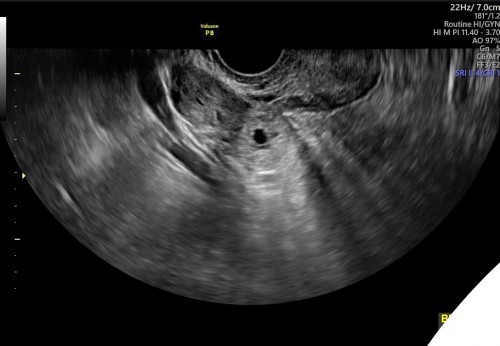

ท้องนอกมดลูกที่ท่อนำไข่ข้างขวา